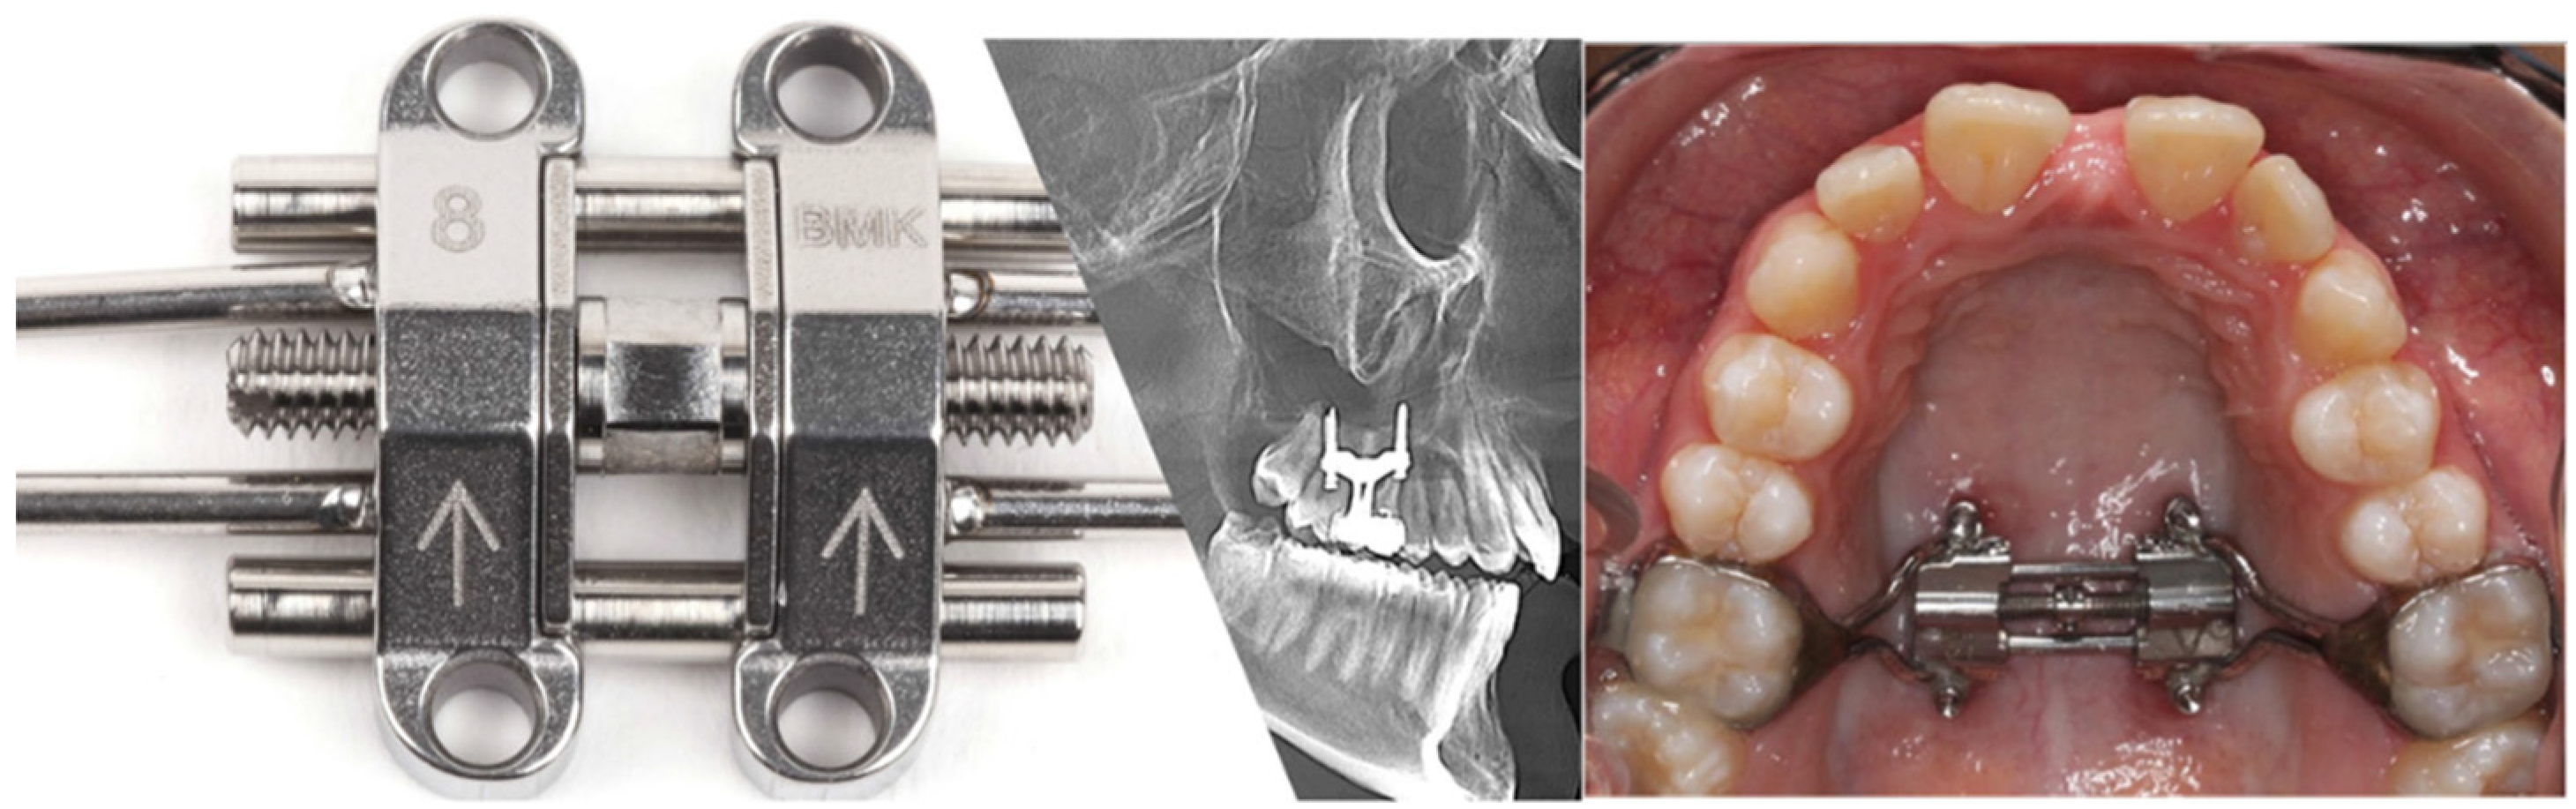

- Carlson, C.; Sung, J.; McComb, R.W.; MacHado, A.W.; Moon, W. Microimplant-assisted rapid palatal expansion appliance to orthopedically correct transverse maxillary deficiency in an adult. Am. J. Orthod. Dentofac. Orthop. 2016, 149, 716–728. [Google Scholar] [CrossRef] [PubMed]

- Cantarella, D.; Dominguez-Mompell, R.; Mallya, S.M.; Moschik, C.; Pan, H.C.; Miller, J.; Moon, W. Changes in the midpalatal and pterygopalatine sutures induced by micro-implant-supported skeletal expander, analyzed with a novel 3D method based on, CBCT imaging. Prog. Orthod. 2017, 18, 1–12. [Google Scholar] [CrossRef]